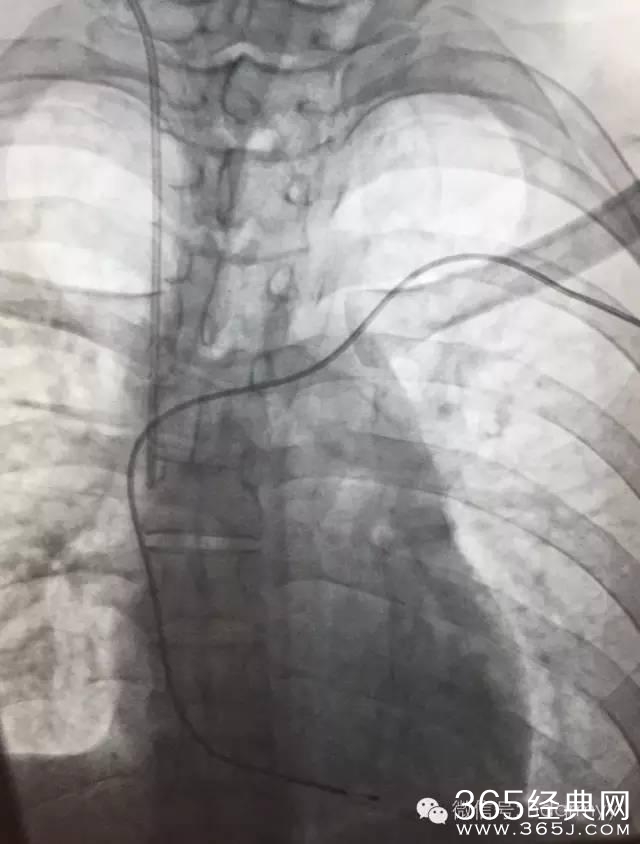

入院后,心内科的值班医生考虑,患者在院前曾出现抽搐、心跳停搏现象,心肌炎较为严重,心脏随时有再次发生停搏的可能,于是马上通知上级医生进行紧急会诊,专家会诊后决定,立即为病人紧急手术安装心脏保护装置-临时起搏器。

手术过程有惊无险,手术在介入科DSA引导下进行,在临时起搏导管送入到右心室时,病人突然出现神志不清、四肢抽搐,心电监护显示患者再次出现心室停搏,手术医生们临危不乱,果断为病人实施各项抢救措施的同时立即连接并启动起搏器。病人心跳马上恢复,随后转醒。经过差不多一个小时,患者顺利安装了临时心脏起搏器,并转入心内科重症监护病区密切观察和治疗。